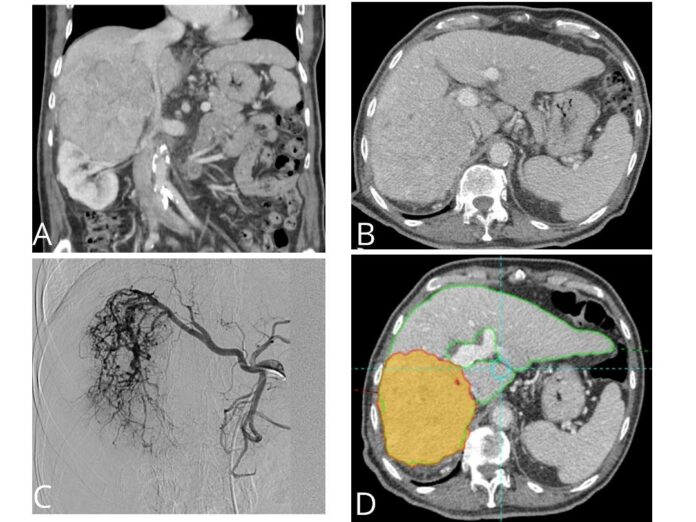

“La radioembolización es una terapia dirigida que consiste en que millones de microesferas de cristal radioactivas con itrio-90 producen una ablación intravascular en el lecho de la lesión”, matiza el doctor, quien indica que “estas microesferas del grosor de un cabello humano se dirigen directamente al tumor hepático a través de la arteria hepática, donde se introducen por medio de un catéter”.

“Las microesferas fluyen directamente hacia el tumor a través de los vasos sanguíneos del propio cáncer y se alojan permanentemente en el mismo y debido a que el procedimiento incide directamente en el tumor, la radiación destruye las células del cáncer con un impacto mínimo sobre el tejido hepático normal adyacente”, afirma.

Además, el especialista añade que “las microesferas seguirán emitiendo radiación durante varias semanas y es una terapia que también se puede utilizar para la reducción del estadío tumoral con el fin de que estos pacientes puedan someterse a una cirugía o trasplante”.